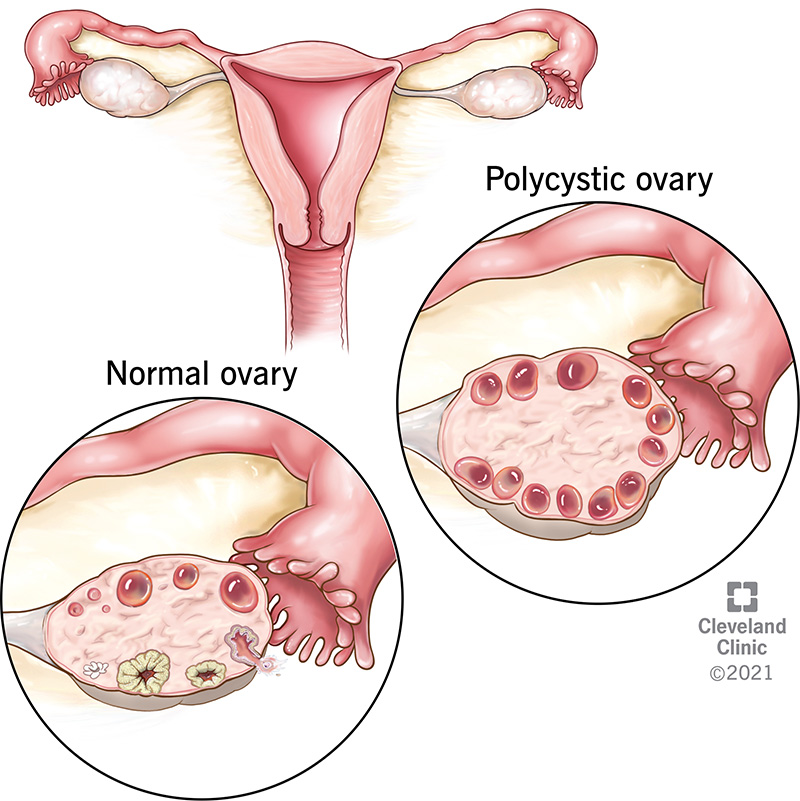

Cysts in the Ovaries: A Misleading Name

The term “polycystic” is often misunderstood. It does not mean you have large, painful cysts that need immediate removal.

In fact, the “cysts” are not true cysts but rather a large number of harmless, underdeveloped follicles (sacs containing eggs) that have stalled in their development due to the lack of proper ovulation.

On an ultrasound, these appear as small, pearl-like formations. It is critical to understand that not all women with PCOS will have polycystic ovaries visible on an ultrasound, and conversely, not all women with polycystic ovaries will have PCOS. Diagnosis requires meeting specific criteria beyond just this single finding.

This can be evident through clinical signs (hirsutism, acne, male-pattern baldness) or confirmed via blood tests. - Polycystic Ovaries on Ultrasound

Showing 12 or more small follicles (2–9 mm in diameter) in one or both ovaries, and/or an increased ovarian volume.

An imaging test to visually examine the ovaries. As mentioned, many cases show a characteristic “string of pearls” appearance—the hallmark of many small, underdeveloped follicles .